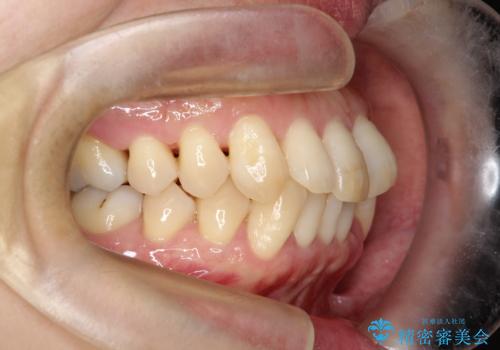

- 前歯の凸凹と前突感を改善するため、上下左右の4番を抜歯し、空いたスペースを利用して前歯を後方へ下げる審美ワイヤー矯正を計画しました。抜歯後は透明で目立ちにくい審美ブラケットを装着し、ワイヤーを用いて徐々に歯列を整えます。毎月1回の調整を通じて歯並びの変化を確認しながら、丁寧に矯正を進め、約2年で理想的な歯列と噛み合わせを完成させることを目指します。

前歯が前に出ていることや歯並びの凸凹が気になるという主訴でした。十分なスペースを確保するため上下左右の第一小臼歯(4番)を抜歯し、そこに前歯を移動させて整列を行いました。矯正装置には目立ちにくい透明なブラケットを選択し、見た目のストレスを軽減。矯正期間中は定期的な通院でワイヤーを微調整し、無理なく確実に歯を動かしました。治療後は前歯が自然な位置に下がり、口元の突出感が解消されるとともに、美しく整った口元に仕上がり、患者様にも大変喜んでいただけました。